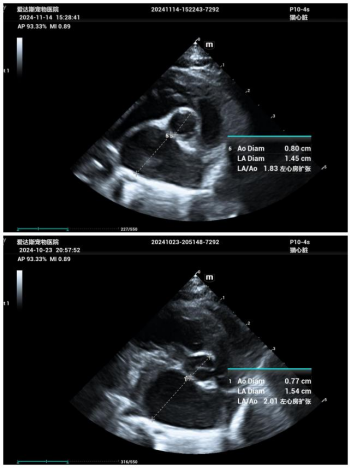

To confirm the diagnosis, we performed an echocardiogram. The results showed an enlarged left atrium and thickened myocardial walls at the end of the left ventricular diastole. These findings indicated that Nana's heart was under significant pressure, leading to heart failure, specifically cardiogenic pulmonary edema, with signs of pneumonia.